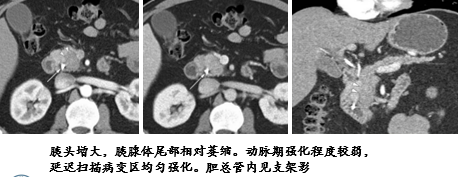

弥漫性伴胆总管改变

CT 表现为胰管及胆总管下段长段狭窄,胆总管下段呈向心性狭窄,狭窄区细长,边缘光整。